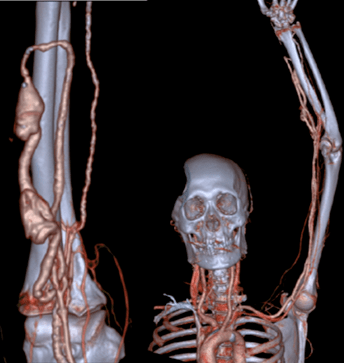

张东亮主任耐心听完患者的叙述 , 给出了诊断:“肿胀手综合征” 。 肿胀手的主要原因是自体动静脉内瘘成型后 , 静脉发生动脉样改变 , 管腔内静水压力升高 , 当静脉血液回流不畅时就会导致压力进一步升高 , 从而形成患侧手臂显著增粗的病症 , 这在起搏器植入的血透患者中 , 发生率更高 。 张主任立刻为老李安排检查:首先是超声明确内瘘吻合口内径 , 发现血管流量尚可 , 静脉弓汇入锁骨下静脉处相对性狭窄伴迂曲 。 随后又进行了上肢及深静脉CT三维重建(CTA+CTV) , 发现主要病变为锁骨下静脉汇入头臂静脉处静脉瓣增生狭窄(如下图)